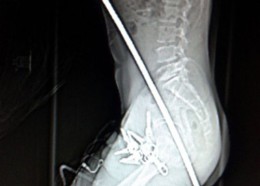

Чудни ренгенски снимки